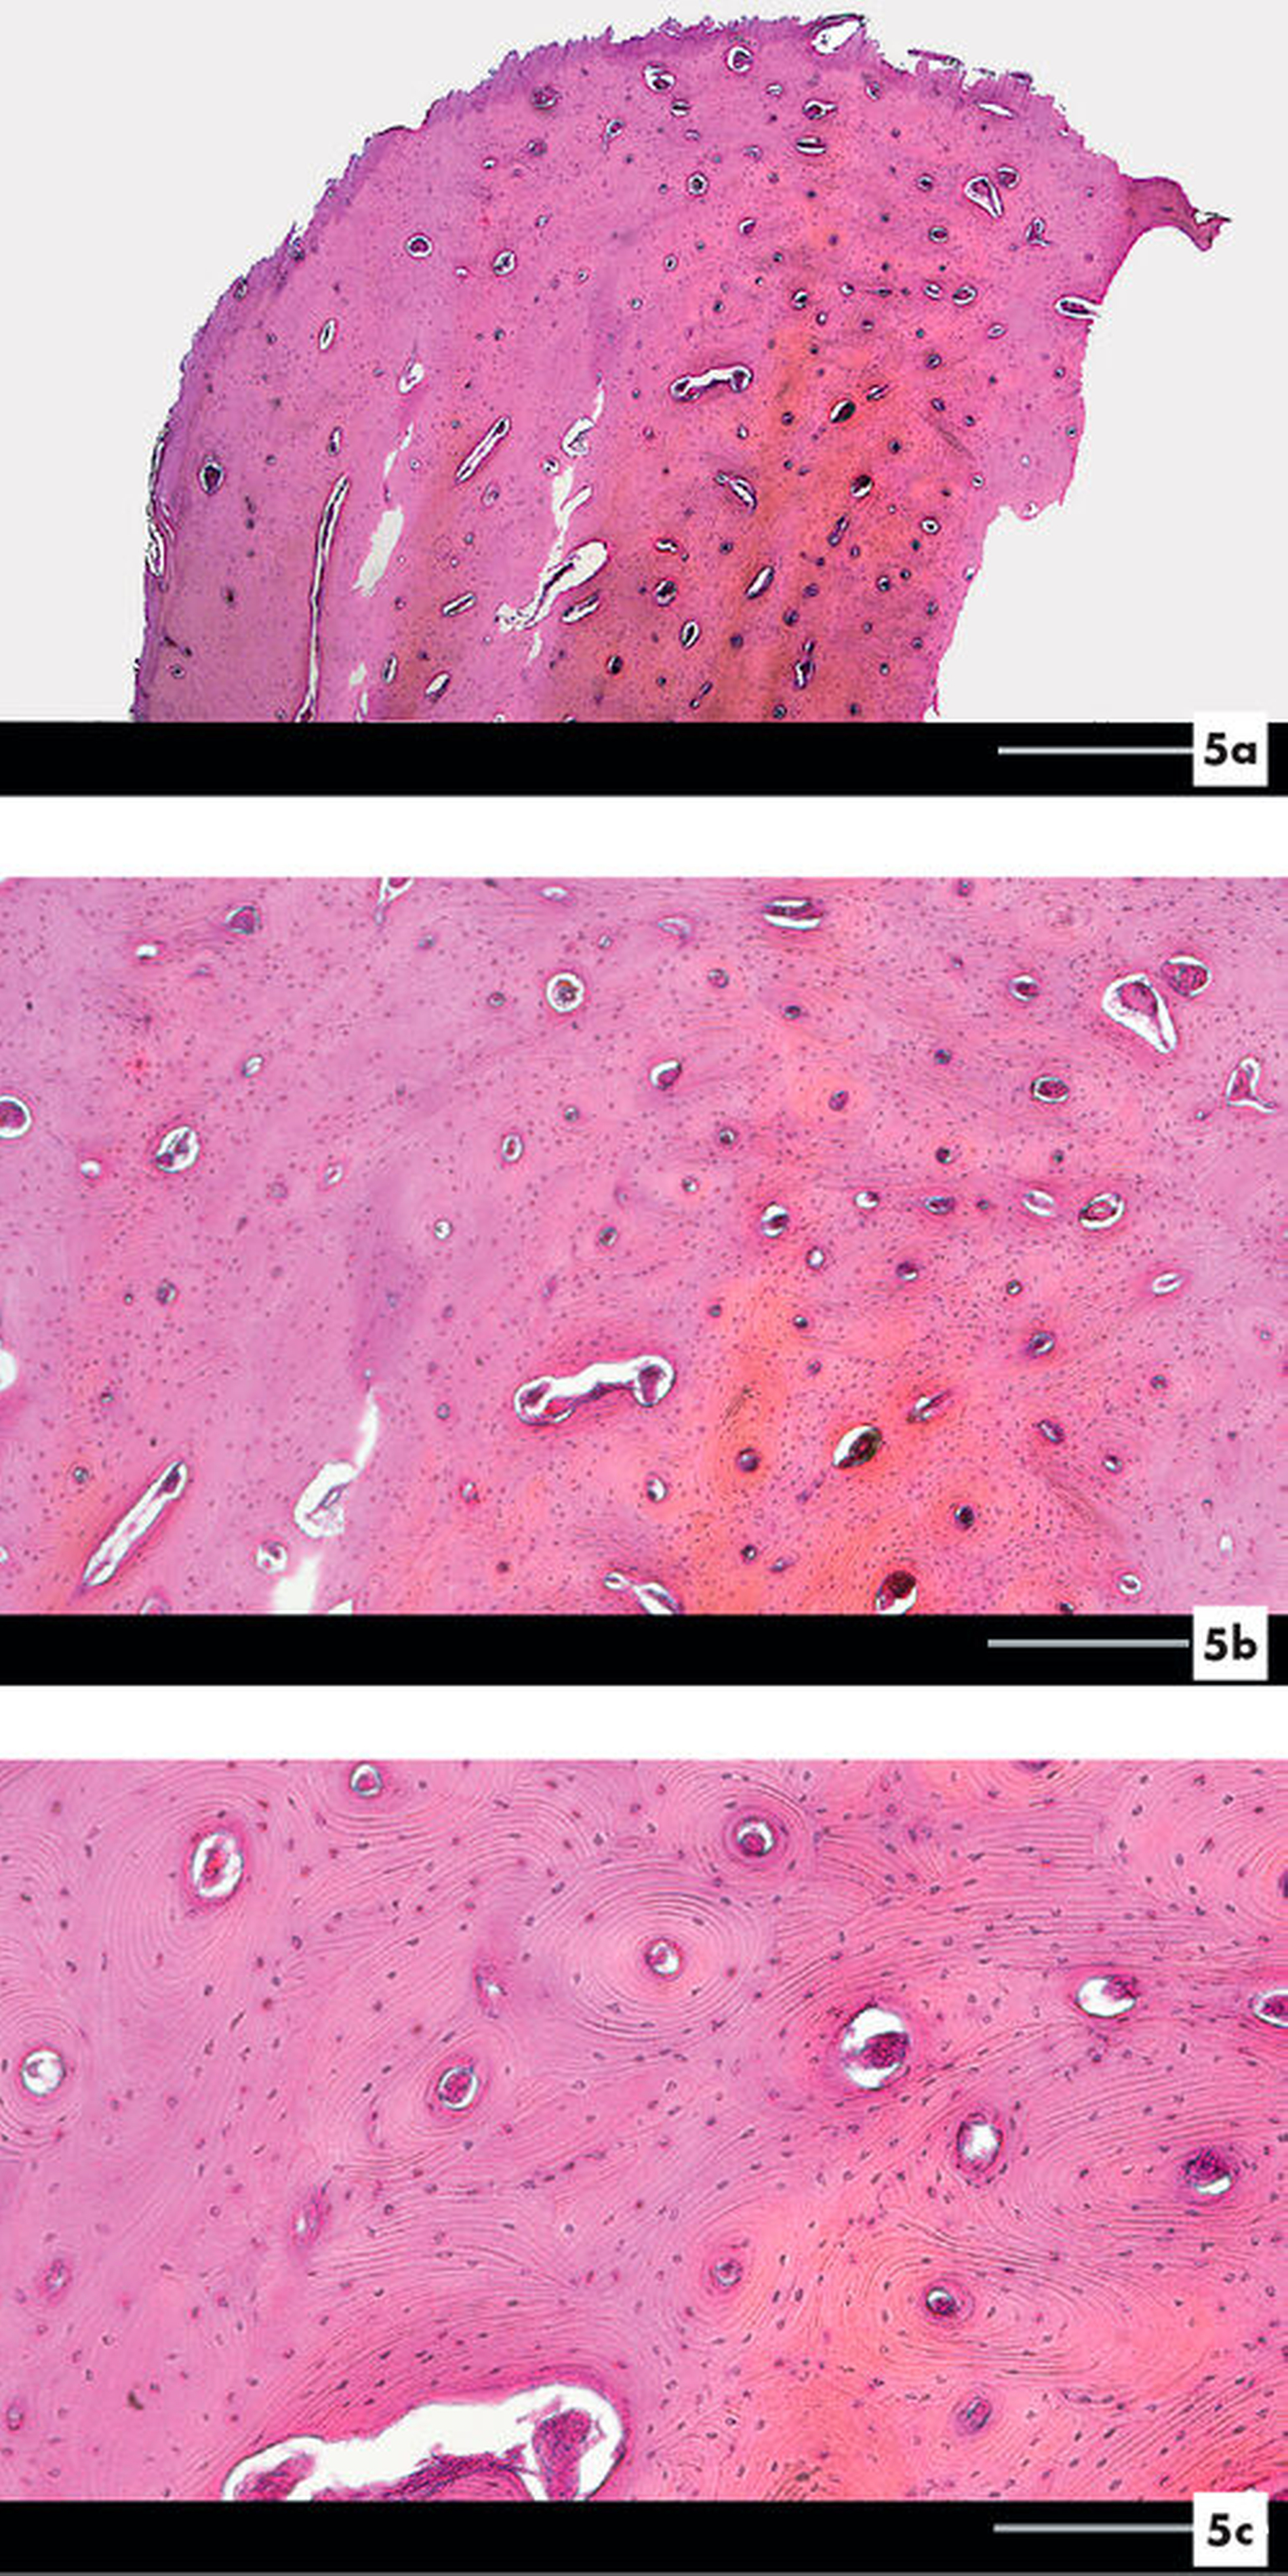

Das Ergebnis der histopathologischen Nachuntersuchung zeigte eine solide, lamellenartige Struktur des eingesendeten Gewebematerials und bestätigte die Verdachtsdiagnose eines peripheren solitären Osteoms (Abbildung 5).

Histologisch unterteilt man das periphere Osteom in das kompakte „Osteoma durum“ und das spongiöse „Osteoma medullare“, wobei ersteres vorwiegend im Bereich der Schädelknochen vorkommt und im Gegensatz zum „Osteoma medullare“ neben einem dichten, lamellären Knochenmaterial keine markhaltigen Hohlräume beinhaltet [Richardson et al., 1999; Manjunatha et al., 2013]. Grundsätzlich ist ein solitäres von einem multilokulären Auftreten zu unterscheiden, wobei ein multilokuläres Vorkommen als erstes Anzeichen für das Vorliegen eines Gardner-Syndroms gewertet werden kann. Bei dieser zumeist autosomal-dominat vererbten Erkrankung kommt es – neben der multiplen Ausbildung von Knochen- (Kiefer- und Mittelgesichtsknochen) und Weichgewebstumoren – zu einer Variante der familiären adenomatösen Polyposis (FAP). Deshalb sollte der klinische Verdacht stets die Untersuchung des Gastrointestinaltrakts zur Folge haben, um die als obligate Präkanzerose bezeichnete FAP frühestmöglich therapieren können [Jones und Korzcak, 1990; Schulze, 2008]. Generell ist die maligne Entartung von Osteomen als äußerste Rarität zu verstehen und das Auftreten von Lokalrezidiven sehr selten beschrieben [Richardson et al., 1999; Woldenberg et al., 2005; Kucukkurt et al., 2016].